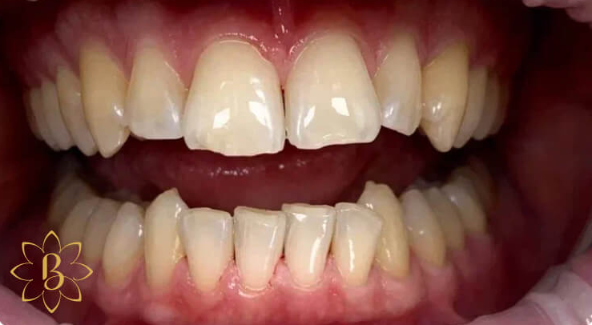

На странице представлено портфолио стоматологий Санкт-Петербурга с работами до и после профессиональной чистки зубов. В нашем портфолио собраны разные клинические случаи: от удаления незначительного налета до снятия массивного поддесневого камня. Здесь вы можете увидеть, как возвращается естественный цвет и внешний вид зубов после процедуры. Изучите результаты до и после чистки зубов, чтобы увидеть реальный эффект и выбрать клинику в Санкт-Петербурге, где профессиональная гигиена поможет вернуть зубам здоровый вид.